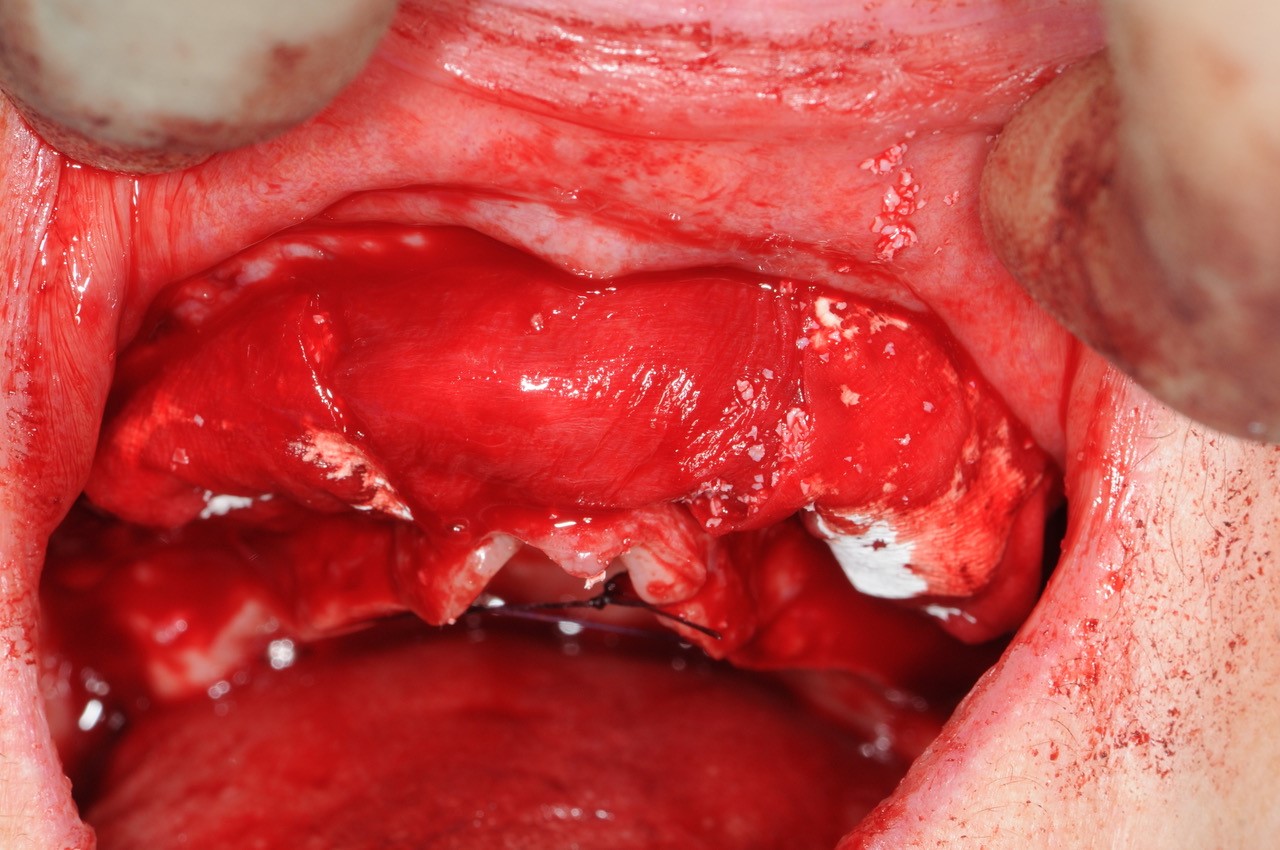

19/21 - Stable bone with approx. 3 mm horizontal bone gain

Reconstruction of maxillary ridge with maxgraft® block - Amit Patel

20/21 - Stable bone with approx. 3 mm horizontal bone gain